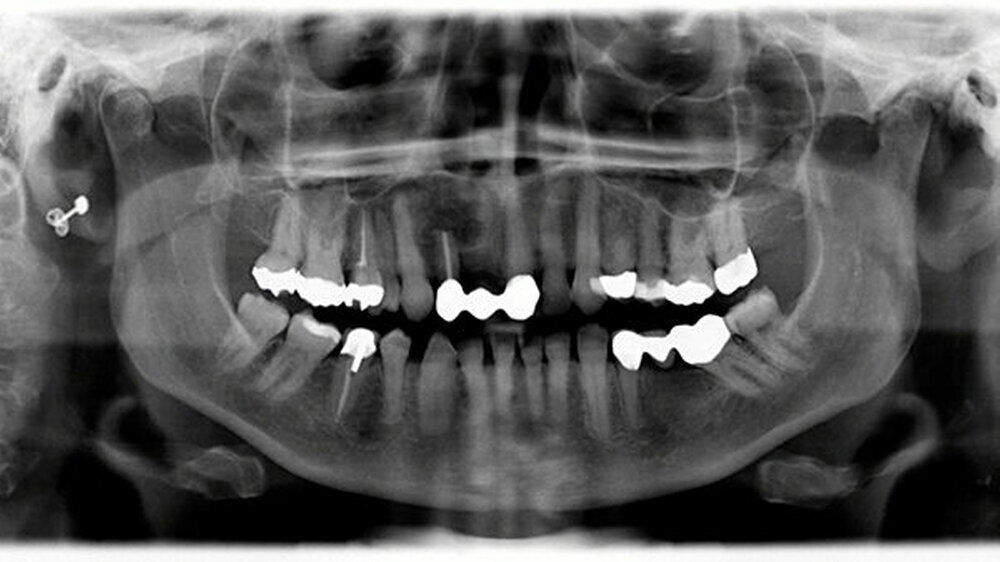

In der Panoramaschichtaufnahme zeigte sich eine Osteolyse im Bereich der Oberkieferfront Regio 12 (Abbildung 2), weshalb eine 3-D-Bildgebung zur Größenbestimmung durchgeführt wurde. Die durchgeführte CT-Diagnostik ergab den Nachweis eines Os librum mit den Maßen 7 x 8 x 11 mm unter Beteiligung der beiden Pfeilerzähne 11 und 13 (Abbildung 3).